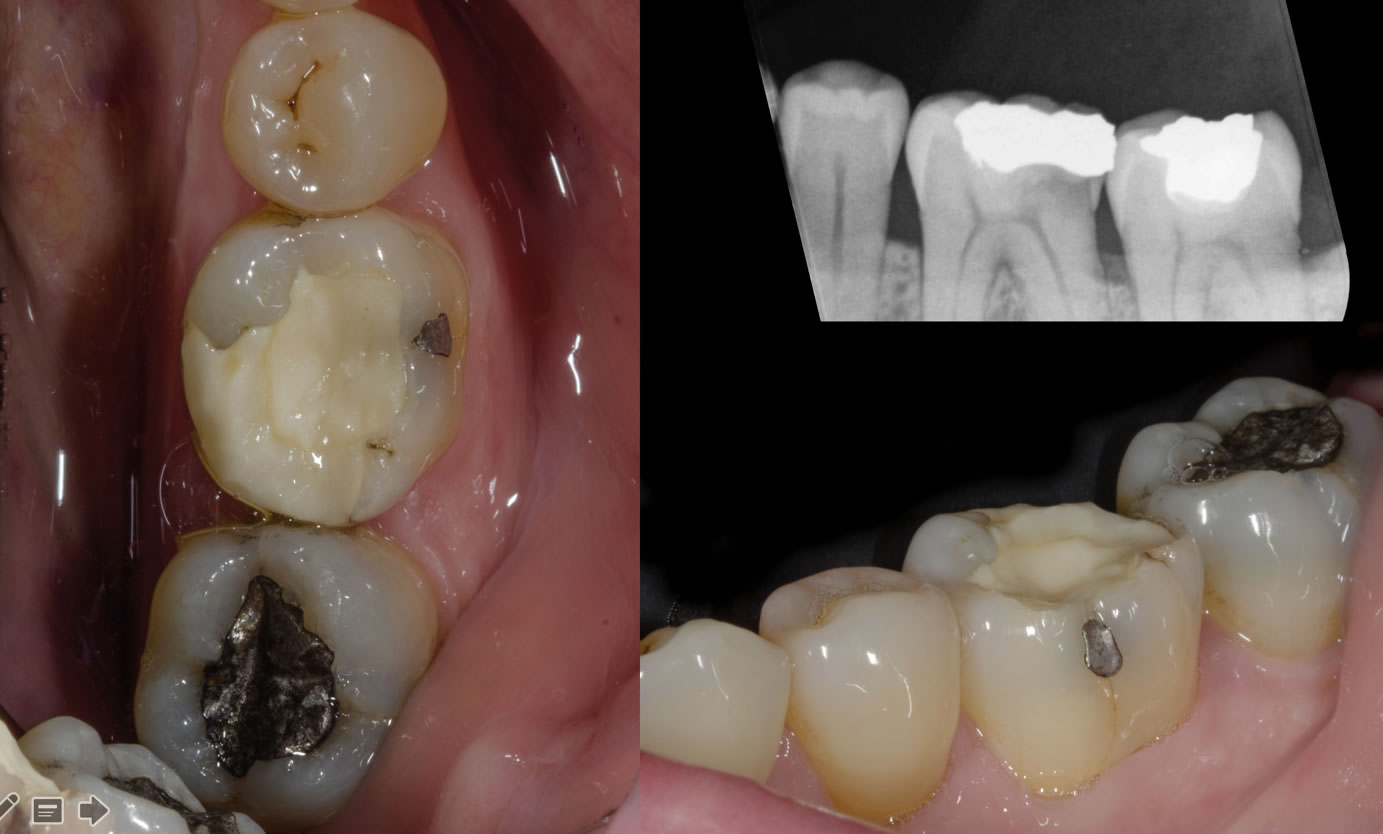

Cas clinique N°1 : overlay Emax sur 14